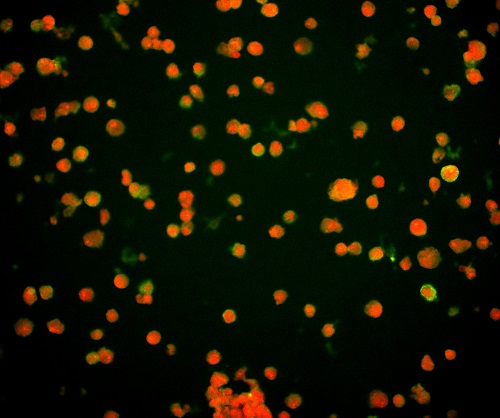

(1)通過觀測對病毒進行特異性標記產生的熒光信號,從而實現對病毒位置數量的判斷。病毒主要由核酸和蛋白質組成,常見的一種方法是利用熒光標記的特異核酸探針與病毒含有的靶DNA分子或RNA分子進行雜交,可通過在熒光顯微鏡下觀察熒光信號,來確定與特異探針雜交后被染色的病毒的分布和數量,這種方式也稱為原位熒光雜交技術(FISH)。

FISH做的病毒檢測,紅色為病毒外殼蛋白

(引自公開論文https://doi.org/10.1073/pnas.1820132117)